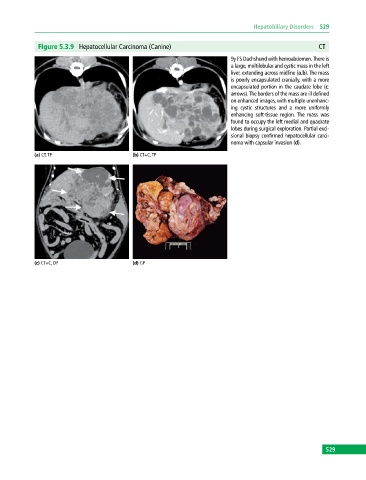

Figure 5.3.9 Hepatocellular Carcinoma (Canine) CT

9y FS Dachshund with hemoabdomen. There is

a large, multilobular and cystic mass in the left

liver, extending across midline (a,b). The mass

is poorly encapsulated cranially, with a more

encapsulated portion in the caudate lobe (c:

arrows). The borders of the mass are ill defined

on enhanced images, with multiple unenhanc-

ing cystic structures and a more uniformly

enhancing soft‐tissue region. The mass was

found to occupy the left medial and quadrate

lobes during surgical exploration. Partial exci-

sional biopsy confirmed hepatocellular carci-

noma with capsular invasion (d).

(a) CT, TP (b) CT+C, TP

(c) CT+C, DP (d) GP